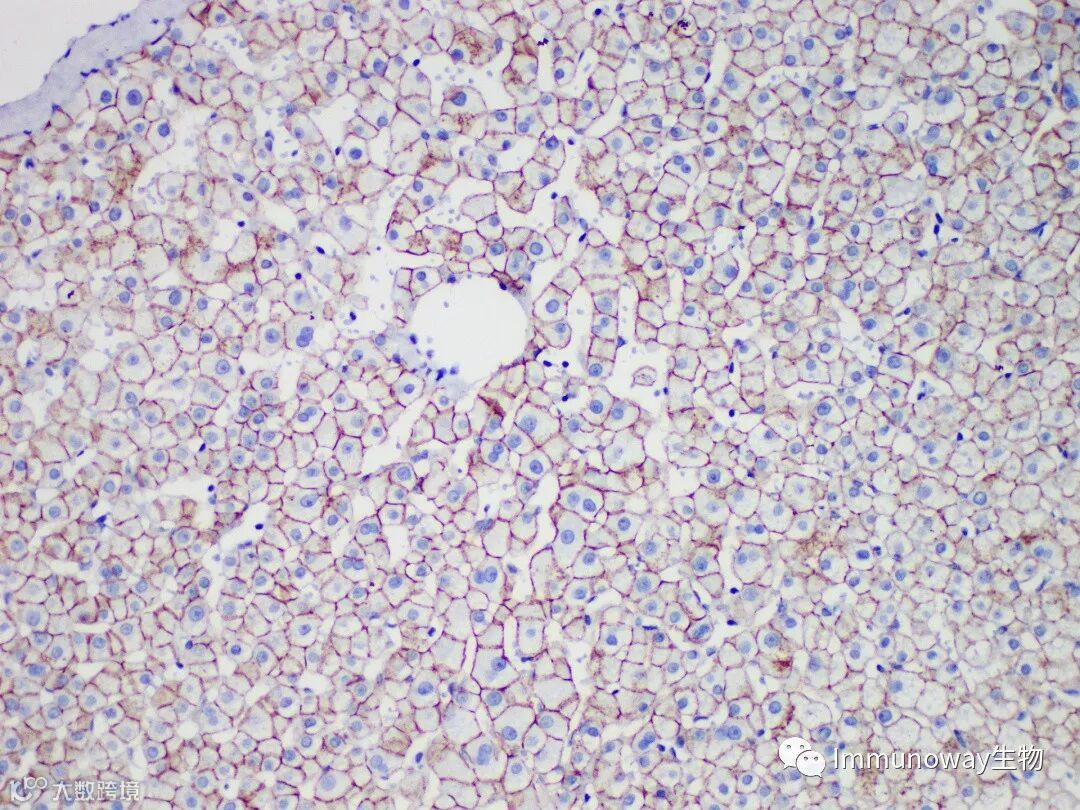

客户结果反馈

检测组织:肝组织石蜡切片

二抗:普通直接酶标记二抗

结论:肝细胞胞浆胞膜弱阳性,低背景

二抗:病理级Polymer酶标记二抗

结论:肝细胞胞浆胞膜强阳性,低背景